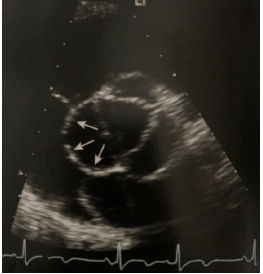

De acordo com a imagem ecocardiográfica abaixo obtida de um paciente jovem assintomático, em avaliação cardiológica de rotina, analise as afirmativas abaixo.

I. Os aneurismas congênitos do seio de Valsalva possuem formas regulares, com seios de paredes finas e invaginadas

II. A ruptura do aneurisma do seio coronário direito ocorre dentro do VD, a do seio coronário esquerdo ocorre dentro do AE e a do seio não coronário ocorre dentro do AD

III. Os aneurismas do seio coronário adquiridos são geralmente decorrentes de traumas torácicos e apresentam formato mais arredondado

IV. O fluxo na fistula da aorta tem seus componentes sistólico e diastólico bem marcados, refletindo a diferença das pressões entre a aorta e a câmara que recebe o fluxo

Estão corretas as afirmativas:

Provas